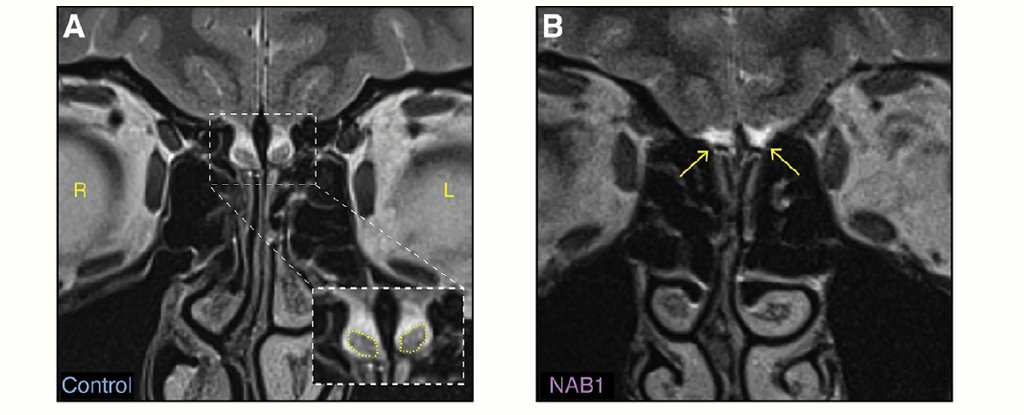

ScienceTechyNews: These Women Can Somehow Still Smell Odours, Despite Missing Their Olfactory Nerves

Scientists aren't yet sure how this is possible.